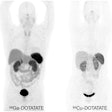

SNMMI issues new guideline for PET imaging of neuroendocrine tumors